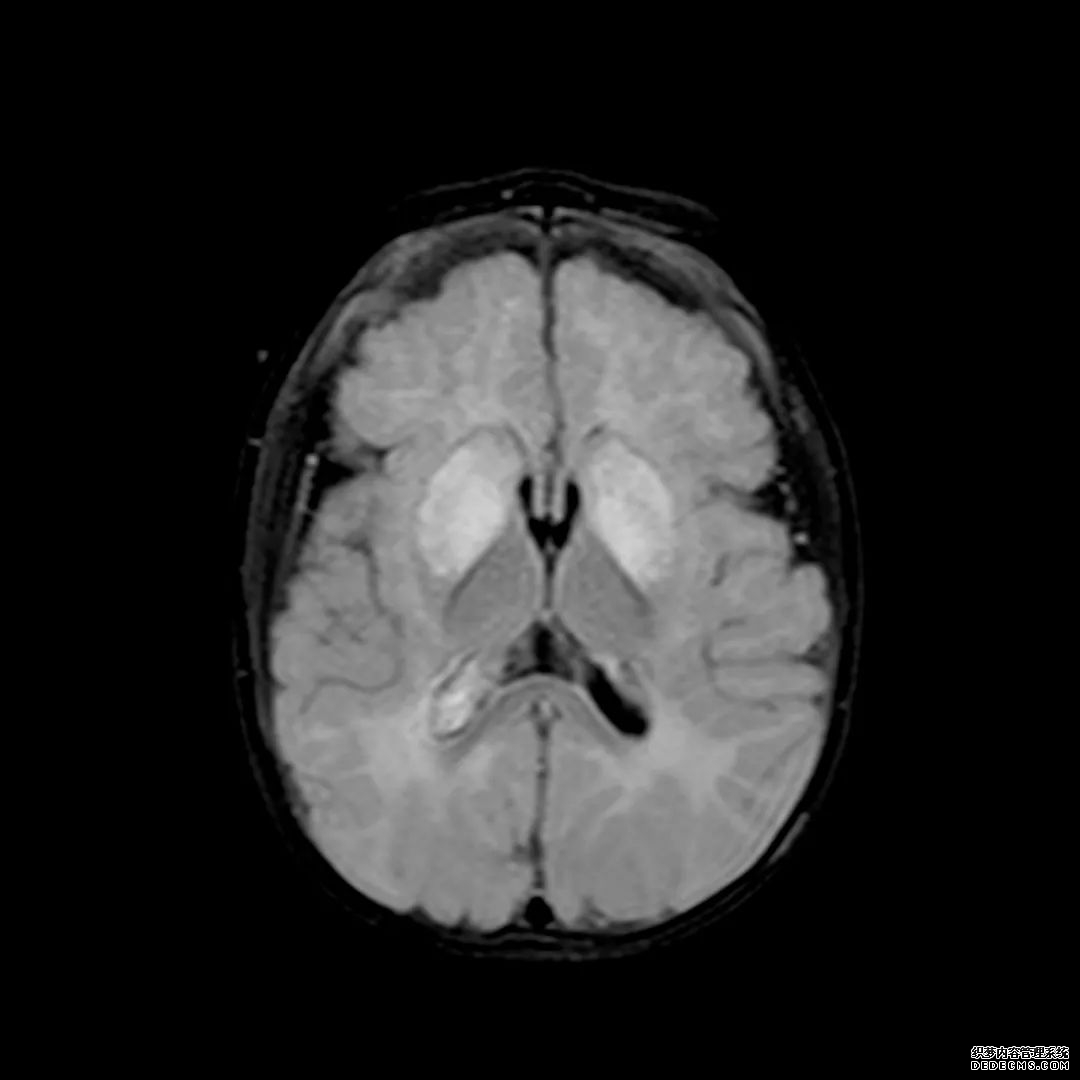

脑MRI显示尾状核、扁豆状核和脑梗头部T2/FLAIR呈双侧对称异常高信号。扩散限制涉及这些区域,其特征是扩散加权DWI(B-1000)上的高强度,ADC图上相应的减弱强度。

印象:通过将这些成像模式与临床和实验室检查结果相结合,就有可能得出低血糖性脑病。

影像影响内囊后肢、大脑皮层(特别是枕叶和岛叶)、海马和基底节区,常是双边对称性的。